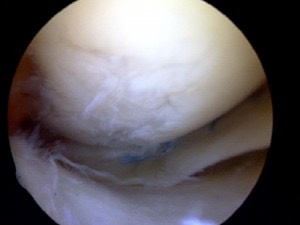

Knee Early Arthritis

Arthroscopic view showing the rough cartilage surface found in arthritis

Knee arthritis is a progressive wearing out of the normal articular cartliage that lines the moving surfaces of the knee.  As the cartilage wears away it can become frayed and rough, and the thickness of the protective cartilage decreases.  This wear and tear can be a slow and progressive process or can develop because of a prior injury.  As the arthritic process progresses it can result in bone rubbing on bone, and become progressively more painful.  The “environment” in an arthritic knee allows the “breaking down” (catabolic effect) process of the cartilage and meniscus to continue.  The wear and tear cycle just continues until the knee is completely worn out.